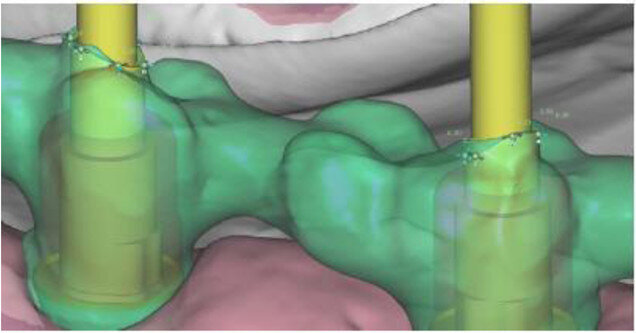

Fig. 12a: Occlusal view showing CAD of the final FDP (a) and detailed screenshot of the interface geometry (b).

Fig. 12b: Occlusal view showing CAD of the final FDP (a) and detailed screenshot of the interface geometry (b).

All six implants osseointegrated successfully without complications. After six months of the patient wearing the provisional FDP, a conventional impression was taken (screw-retained impression copings, open-tray technique, polyether material) to fabricate the final FDP on a new, precise cast (Fig. 11), which was then digitised with a laboratory scanner (Deluxe scanner, Open Technologies). The final framework was designed with straight connection to the implant platforms and with a cutback allowing for the veneering material (Figs. 12a & b). While the cobalt– chromium framework was fabricated using CAD/CAM technology (exocad, exocad; M1 Wet, Zirkonzahn), the veneering was performed manually, allowing for individual characterisation of the teeth (Figs. 13a–d). The models were fabricated with a laser stereolithography printer (XFAB) using an ABS-like polymer (Precisa RD096B, DWS). Healthy mucosal conditions were present at the delivery of the final CAD/CAM restoration, made from cobalt–chromium and composite veneering material (Figs. 14a–e). The accurately fitting FDP was attached with screws at 25 Ncm and the screw access area covered with composite material. The panoramic radiograph on the day of delivery showed optimal prosthetic and osseous conditions (Fig. 15). The patient followed a regular maintenance programme at the dental hygienist twice a year.